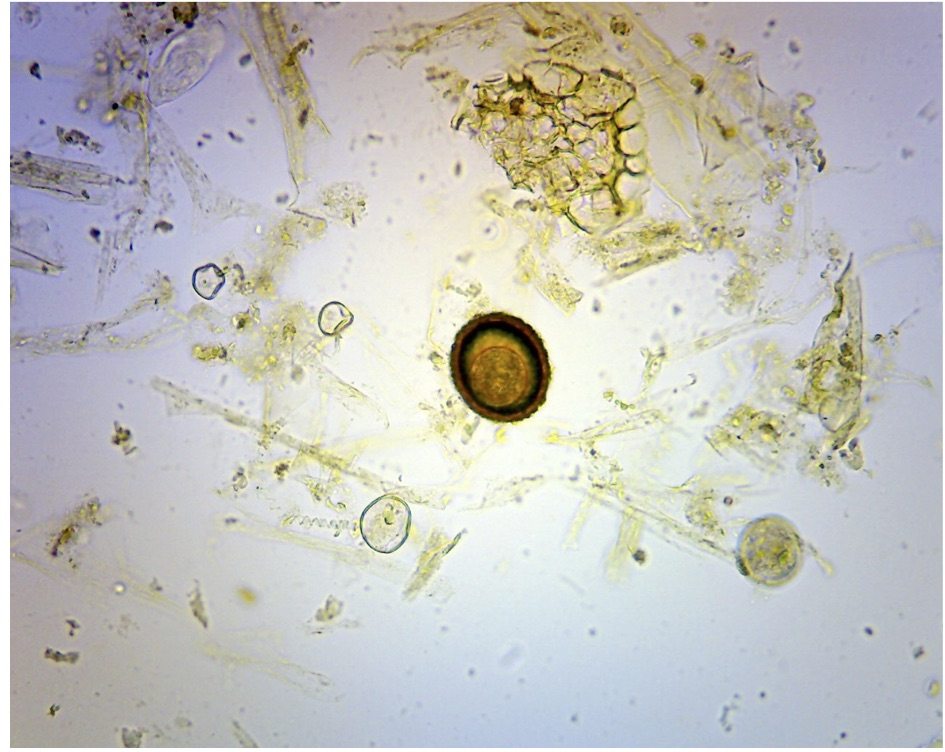

In order to make this decision process more transparent we have implemented a “worming package”, in which the diagrams below form the basis of our treatment protocol.

This package includes us assessing your specific horses risk in its given population. We will use the diagrams below to select which animals need treatment, which need monitoring and coupled with advice on pasture management we hope to keep worm burdens to an acceptable level.